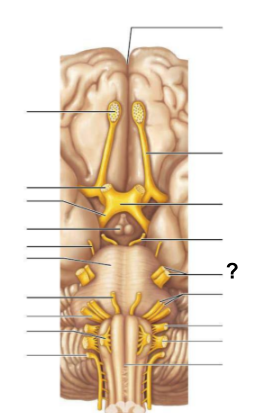

After the third ventricle, CSF flows through which narrow passage, labeled “?”, to reach the fourth ventricle?

Cerebral aqueduct